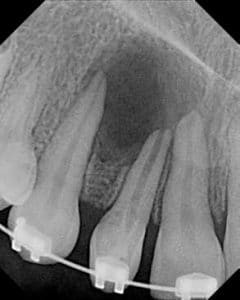

24. (Select ONE OR MORE correct answers.)

Which of the following may complicate the root canal treatment on tooth 3.5?

25. (Select ONE OR MORE correct answers.)

Which of the following may complicate the root canal treatment on tooth 1.2?